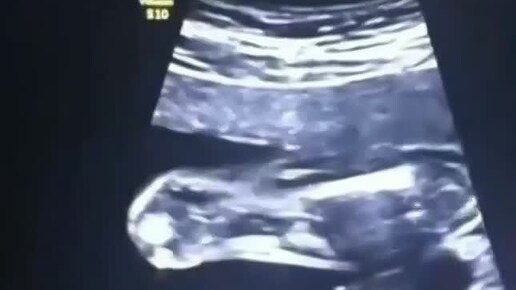

Точность УЗИ в одном ролике

«Размер XXXL: факты и приколы»